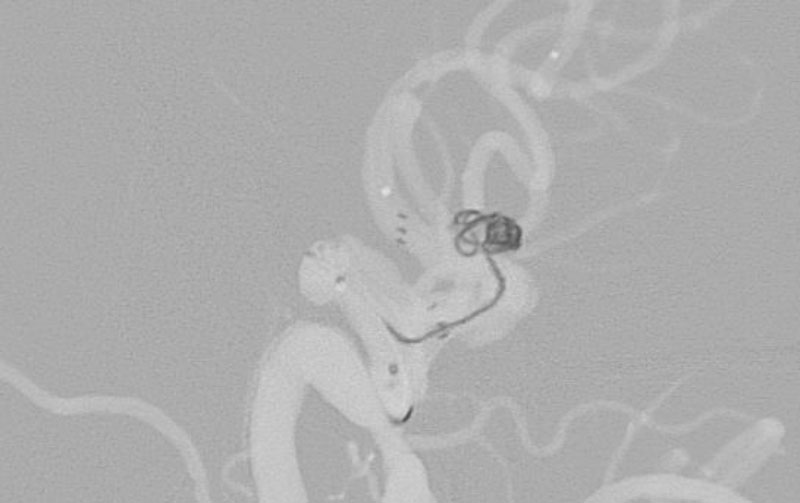

No.1617 手術中